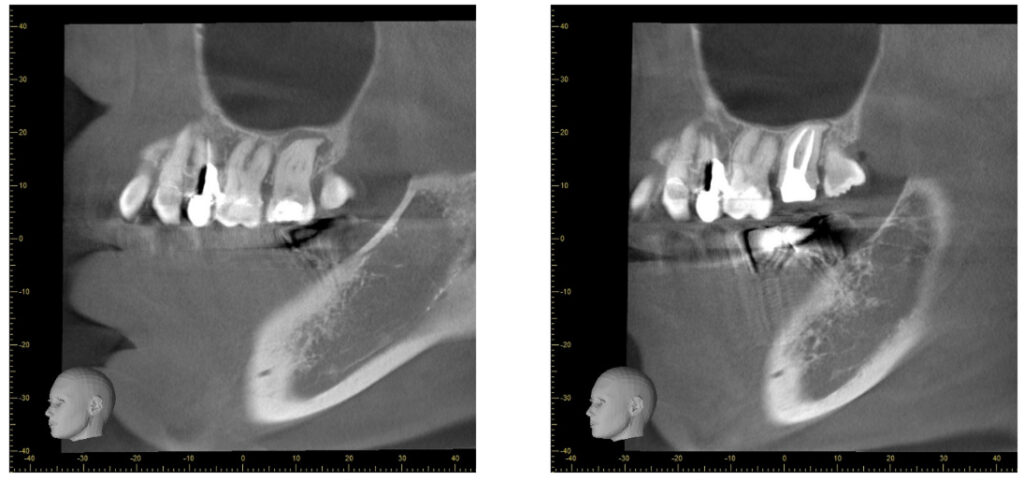

症例24:根尖性歯周炎

何もしてなくても痛い、腫れている

50代女性、他院で断られた歯を精密根管治療させていただきました。

根尖部の炎症の改善、再感染の防止、審美性の改善を行いました。